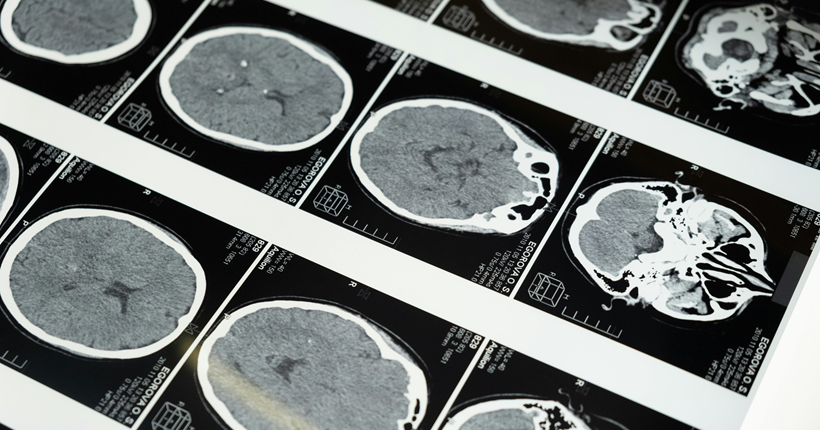

La importancia del diagnóstico precoz en el ámbito de las demencias

El diagnóstico precoz en el ámbito de las demencias es fundamental debido a su impacto positivo tanto en la calidad de vida de las personas afectadas como en la planificación de su atención médica y social. A continuación, se detallan las principales razones que subrayan su importancia:

Desafíos para el diagnóstico precoz

A pesar de sus beneficios, el diagnóstico temprano enfrenta retos, como:

- Reconocer los primeros síntomas, que a menudo son sutiles y se confunden con el envejecimiento normal.

- Estigmas sociales y falta de conocimiento, que retrasan la búsqueda de ayuda.

- Acceso limitado a especialistas en algunas regiones, lo que dificulta una evaluación adecuada.

En conclusión, el diagnóstico precoz de las demencias es una herramienta esencial para abordar la enfermedad de manera proactiva, empoderar a las personas afectadas y sus familias, y optimizar la atención en todas las etapas del proceso. Fomentar la sensibilización y mejorar el acceso a servicios de evaluación y diagnóstico son pasos clave hacia este objetivo.